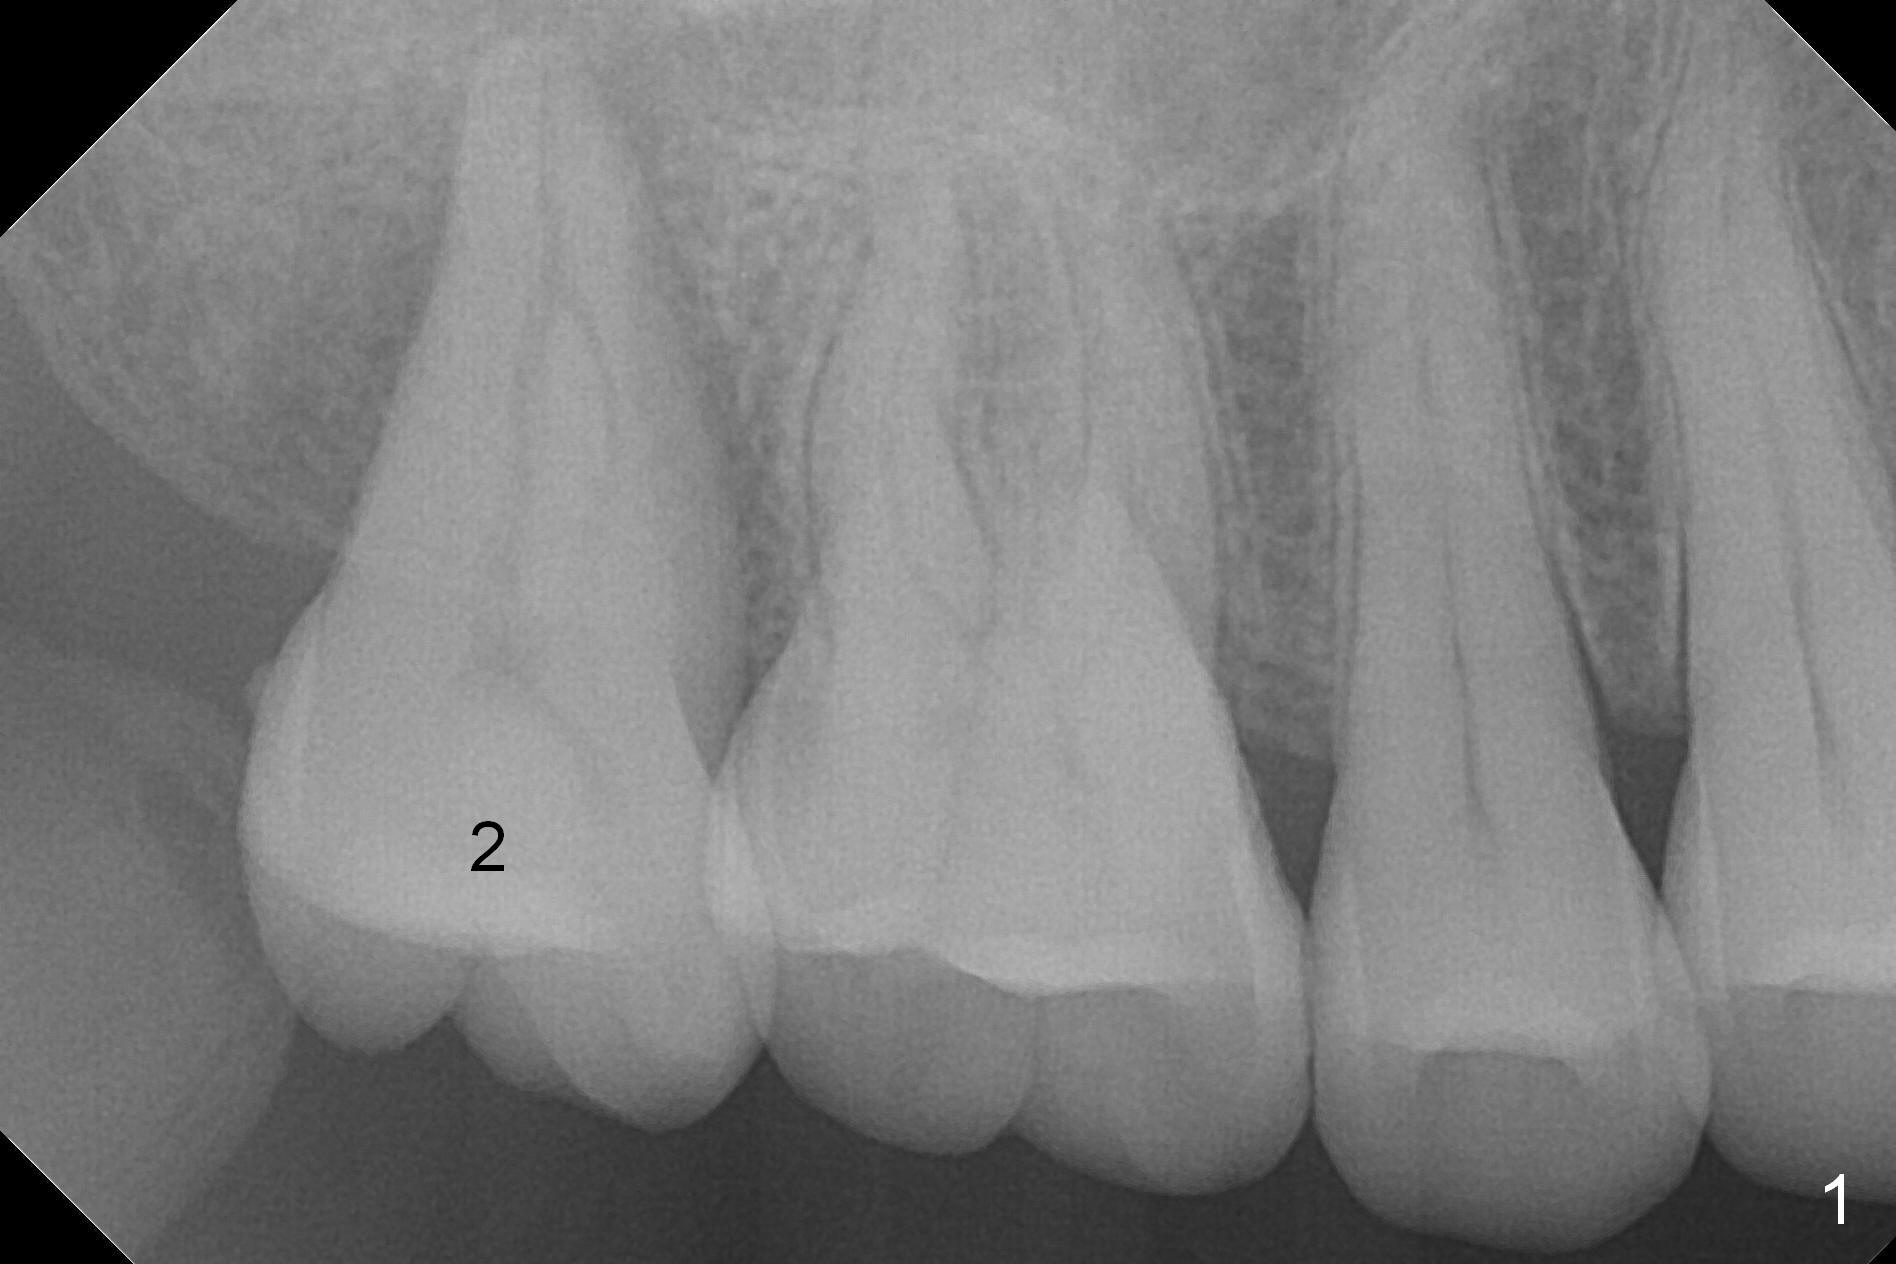

Implant Is Inserted into Socket for Stability

A 53-year-old man agrees implant treatment for crack tooth #2 (Fig.1). Since the apex overlaps the sinus floor (Fig.2 panoramic X-ray), the primary stability will be derived from tight contact of an implant with the socket. After extraction (Metronidazole), osteotomes are going to be used to break through the sinus floor (RT2-4), followed by tap drills (4.5 mm or larger (Fig.3) until achieving 35 Ncm). The implant will be one size larger. Prepare regular and extra wide surgical kits. Before implant placement, insert PRF plug and allograft/Osteogen.